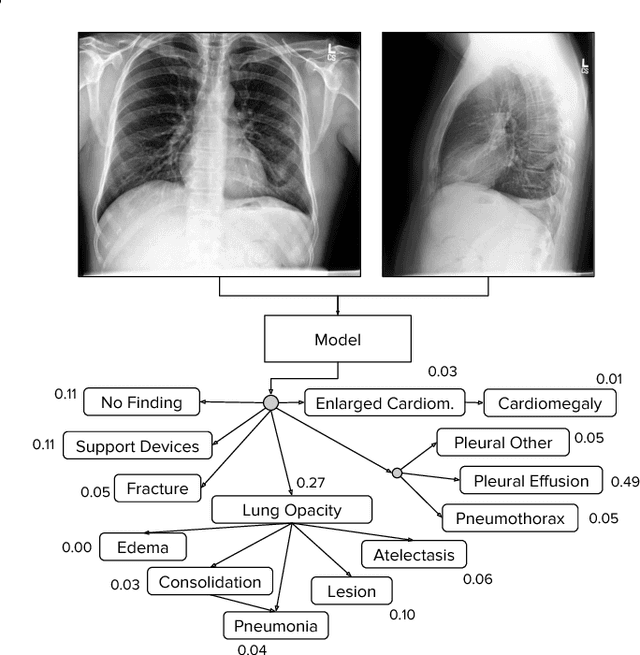

Abstract:Large, labeled datasets have driven deep learning methods to achieve expert-level performance on a variety of medical imaging tasks. We present CheXpert, a large dataset that contains 224,316 chest radiographs of 65,240 patients. We design a labeler to automatically detect the presence of 14 observations in radiology reports, capturing uncertainties inherent in radiograph interpretation. We investigate different approaches to using the uncertainty labels for training convolutional neural networks that output the probability of these observations given the available frontal and lateral radiographs. On a validation set of 200 chest radiographic studies which were manually annotated by 3 board-certified radiologists, we find that different uncertainty approaches are useful for different pathologies. We then evaluate our best model on a test set composed of 500 chest radiographic studies annotated by a consensus of 5 board-certified radiologists, and compare the performance of our model to that of 3 additional radiologists in the detection of 5 selected pathologies. On Cardiomegaly, Edema, and Pleural Effusion, the model ROC and PR curves lie above all 3 radiologist operating points. We release the dataset to the public as a standard benchmark to evaluate performance of chest radiograph interpretation models. The dataset is freely available at https://stanfordmlgroup.github.io/competitions/chexpert .